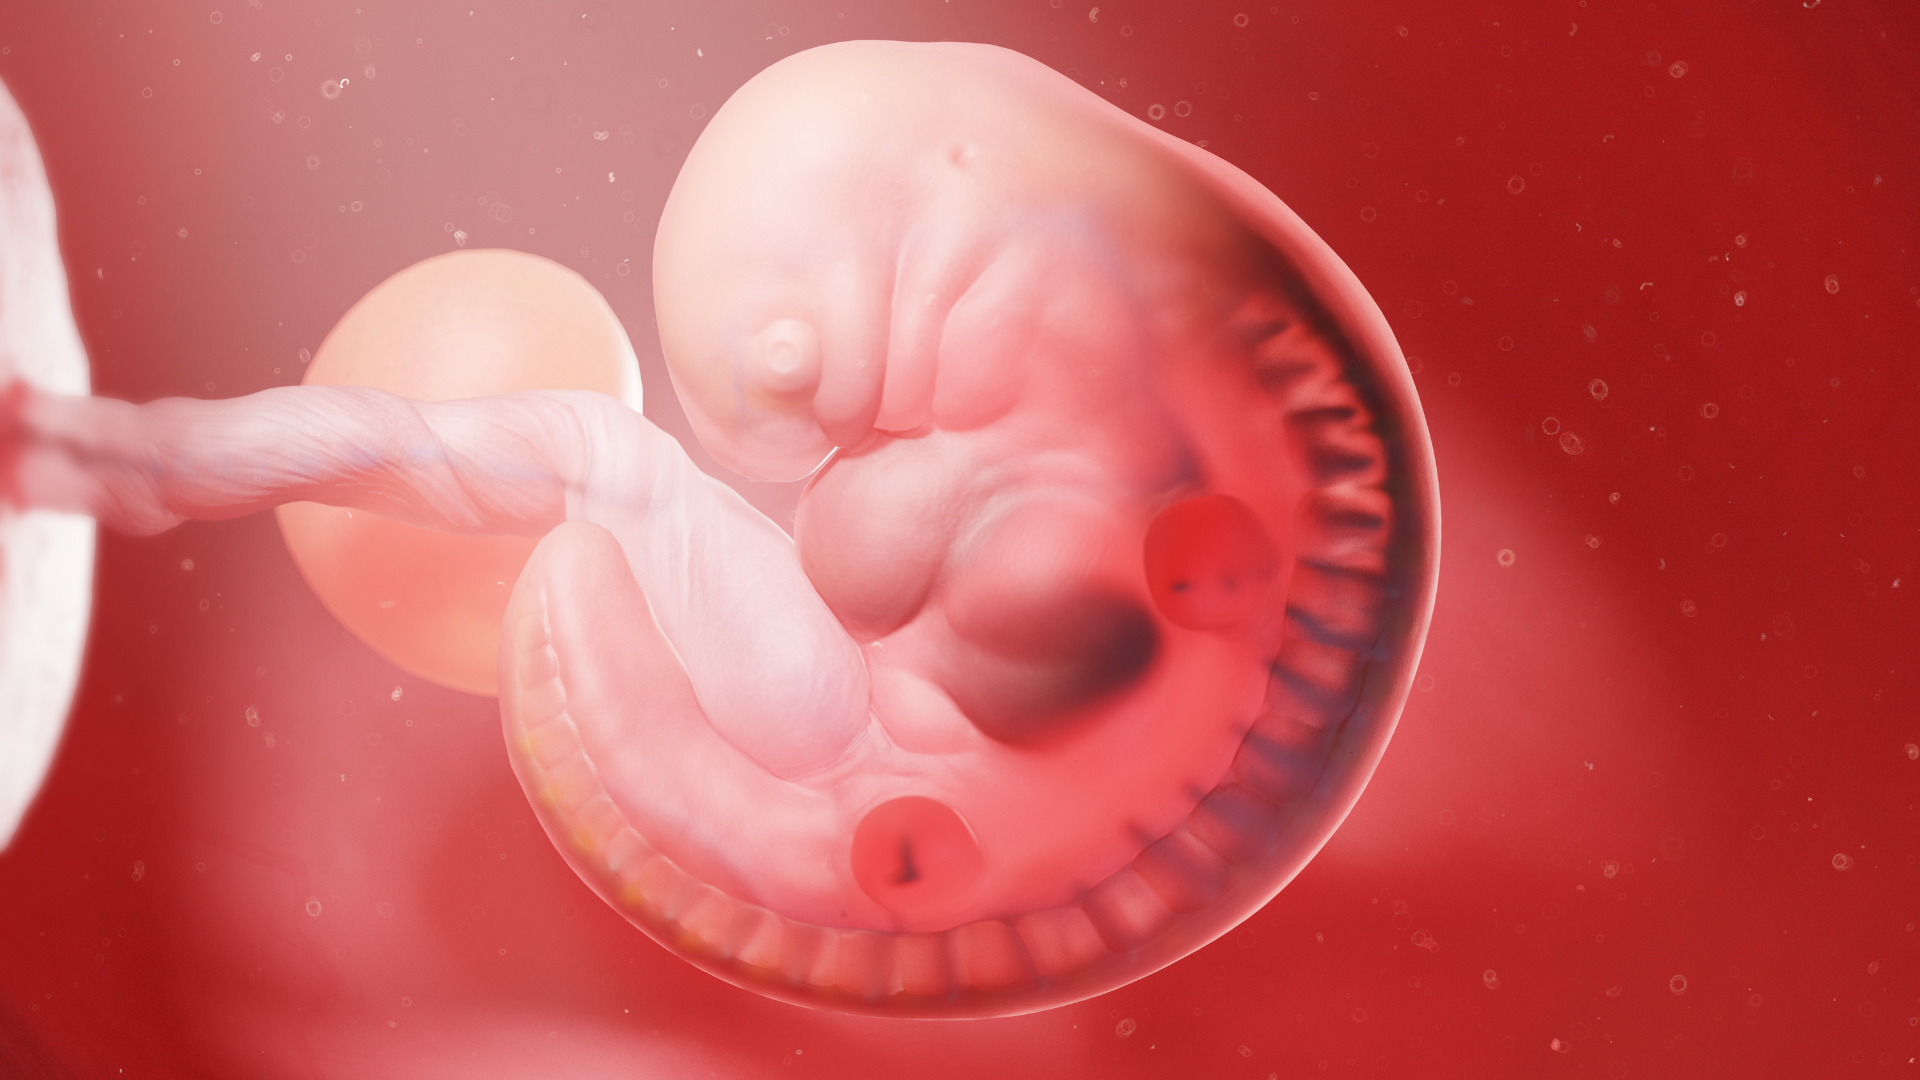

Nước ối là chất dịch lỏng trong suốt bao quanh thai nhi, nằm bên trong túi ối và được xem như “lá chắn sinh học” đầu tiên bảo vệ bé trước những tác động từ môi trường tử cung. Từ khi mới hình thành phôi thai, nước ối đã đóng vai trò quan trọng và duy trì suốt toàn bộ thai kỳ.

Nguồn gốc nước ối thay đổi theo từng giai đoạn. Ở ba tháng đầu, nước ối chủ yếu được tạo ra từ huyết tương của mẹ thấm qua màng ối. Bước sang giai đoạn giữa và cuối thai kỳ, nước ối chủ yếu đến từ nước tiểu của thai nhi, dịch từ phổi, hệ hô hấp và da thai. Nhờ sự trao đổi liên tục giữa mẹ - màng ối - thai nhi, nước ối luôn được làm mới và duy trì ở mức ổn định.

Nước ối xuất hiện rất sớm, từ khoảng ngày thứ 12 sau thụ thai. Lượng nước ối tăng dần theo sự phát triển của thai nhi, đạt khoảng 800 - 1000 ml ở tuần 34 - 36, sau đó giảm nhẹ ở cuối thai kỳ. Đây là môi trường sống có tính đệm, vô trùng và giàu dưỡng chất cần thiết cho sự phát triển của thai.